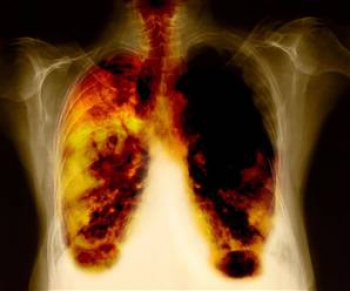

Akciğer Kanseri Nedir?

Akciğerler Kanserler genellikle ilk ortaya çıktığı dokuya göre adlandırılır. Akciğer kanseri ilk önce akciğerde başlar. Küçük hücreli akciğer kanseri akciğer dokularında kanser (habis, kötü huylu) hücrelerinin bulunduğu bir hastalıktır. Akciğerler göğüs boşluğumuzun büyük kısmını dolduran koni şeklinde, süngerimsi yapıda bir çift organdır.

Yukarıdaki belirtilerle ve bulgularla hekime başvuran hastalarda ayrıntılı bir öykü ve fizik muayenenin ardından tanı için atılacak ilk adım standart akciğer grafisi (2 yönlü) çekilmesidir. Birçok olguda bu görüntüleme yöntemi ile tümör ya da tümörün oluşturduğu enfeksiyon, plörezi, atelektazi (akciğerin çökmesi) gibi tablolar saptanabilir. Akciğer grafisinde tümör ya da tümör ile ilişkili olabilecek diğer görünümlerin saptanması halinde atılacak 2. adım genellikle akciğerin bilgisayarlı tomografisinin çekilmesidir. Bilgisayarlı tomografi görülen lezyon hakkında detaylı bilgi verdiği gibi standart akciğer grafisinde görülemeyecek kadar küçük olan diğer lezyonların görülmesine de olanak sağlar. Standart akciğer grafisi ve bilgisayarlı tomografilerin incelenmesinden sonra hastalığın bölgesel yayılımı ve lokalizasyonu ortaya çıkar. Hekim bu noktada artık kesin tanı için gerekli olacak biyopsi yönteminin ne olacağına karar verebilir. Örneğin cerrahi müdahale düşünülen olgularda ve santral bölgede yer alan tümörlerde bronkoskopi yapılması hem evreleme hem de tanı için gerekli iken, bronkoskopi ile ulaşılamayacak periferik bölgelerde yer alan tümörlerde bilgisayarlı tomografi rehberliğinde iğne biyopsisi tercih edilebilir. Yine bu ilk incelemelerin sonucunda tümöre cerrahi bir girişim düşünülmüyorsa tanı için ilk aşamada balgam muayenesi istenebilir. Bu tür hastalarda balgamın sitolojik incelemesi sonucunda tanıya ulaşılamaz ise diğer yöntemlere başvurulur.